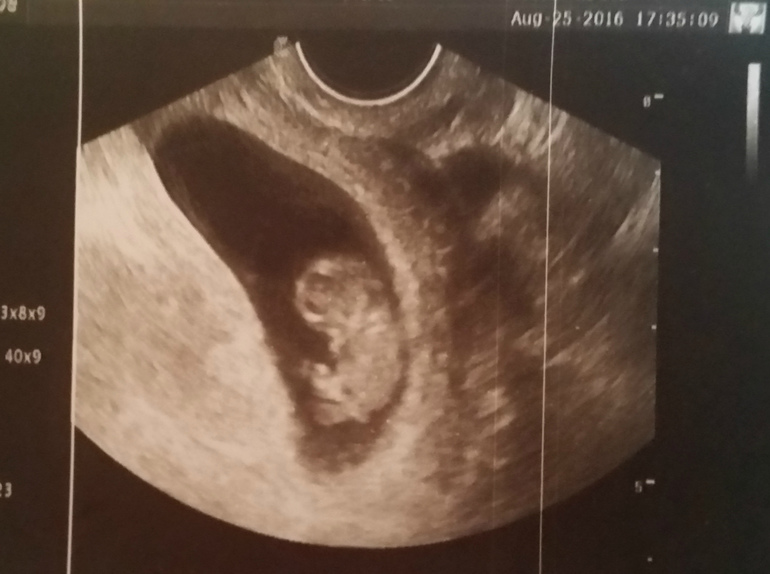

Узи на 9й неделе.

Все хорошо, мы растем КТР 23мм что соответствует 9 неделям, никакой кисты она не увидела( хотя на 1м УЗИ в 6 недель нашли кисту) может рассосалась....

Мне кажется наш малыш такой красивый на этом снимке